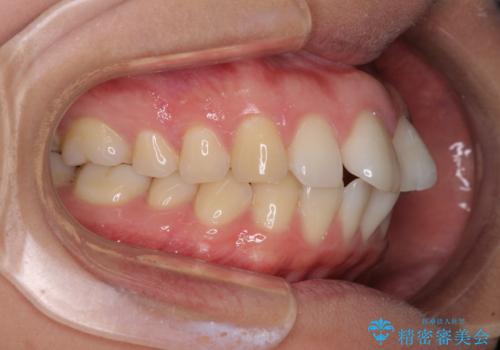

- 前歯の出っ歯と口元の閉じにくさを気にして来院された患者様です。

口元を積極的に引っ込めるために、上下左右の小臼歯4本を抜歯することとしました。

4本の歯を抜歯したことで、飛び出していた口元が引っ込み、横顔が大きく改善されました。

咬み合わせが悪化することのないようにスペースを閉じていくことができ、比較的スムーズに治療を進めることができました。